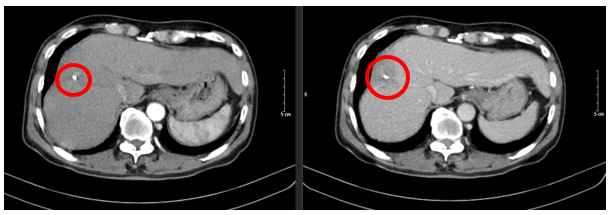

Ngày 19/06/2024: (sau 7 chu kì)

Hình 4: Hình ảnh chụp cắt lớp vi tính ổ bụng: Nhu mô vùng ngoại vi sát bao gan hạ phân thùy VII - VIII có đám (vòng tròn đỏ) giảm tỉ trọng kích thước ~ 28x36mm, trong có lắng đọng vật liệu nút mạch, không có huyết khối

Ngày 26/12/2024: (sau 17 chu kì)

Hình 5: Hình ảnh chụp cắt lớp vi tính ổ bụng: Nhu mô vùng ngoại vi sát bao gan hạ phân thùy VII - VIII có đám (vòng tròn đỏ) giảm tỉ trọng kích thước ~ 21x48mm, trong có lắng đọng vật liệu nút mạch, sau tiêm không ngấm thuốc, không có huyết khối.

Ngày 03/03/2025: (sau 20 chu kì)

Hình 6: Hình ảnh chụp cắt lớp vi tính ổ bụng: Nhu mô vùng ngoại vi sát bao gan hạ phân thùy VII - VIII có đám (vòng tròn đỏ) giảm tỉ trọng kích thước ~ 22x45mm, trong có lắng đọng vật liệu nút mạch, sau tiêm không ngấm thuốc, không có huyết khối.

Nhận xét: Bệnh nhân đạt đáp ứng tốt với điều trị: khối u thu nhỏ kích thước đáng kể sau 20 chu kì (từ 81x51mm xuống 22x45 mm). Đánh giá theo tiêu chuẩn RECIST 1.1, bệnh đáp ứng một phần (PR – Partial Responce).